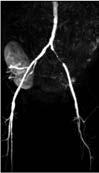

Periphere Gefäßdarstellung (pAVK-Diagnostik)

MR- und CT-Angiographie: In den letzten Jahren hat sich die nichtinvasive Bildgebung mittels MRA und CTA auch im Bereich der Darstellung der peripheren Arterien zu einer äußerst zuverlässigen Alternative zur DSA entwickelt. Die CTA und MRA sind beides hochpräzise Methoden, die eine genaue, detailgetreue Darstellung der arteriellen Anatomie, der artherosklerotischen Plaques und der Verengung des peripheren Gefäßsystems von der Aorta bis hinunter zu den Füßen ermöglichen (Abb. 6a, b). Mit beiden Verfahren lässt sich eine pAVK nicht nur zuverlässig darstellen, auch der Stenosegrad kann bestimmt werden. Beide Verfahren können zur Behandlung des gesamten Spektrums von Patienten mit

Abb. 5a Abb. 5b

Abbildung 5a, b: Darstellung der Aorta.

a: Mit MR-Angiographie erhobene Übersicht.

b: CTA-Darstellung einer langstreckigen Aortendissektion Typ A.

Abb. 6a

Abb. 6b

Abbildung 6a, b: Darstellung peripherer Arterien.

a: Die MR-Angiographie der distalen Aorta bis zum Femoralbereich zeigt einen Verschluss der A. femoralis superficialis (AFS) links sowie einen iliakalen Stent links.

b: CT-Angiographie der Bifurkation der Aorta abdominalis.

vermuteter oder bekannter pAVK eingesetzt werden. Hinsichtlich der diagnostischen Genauigkeit und dem Nachweis sowie der Einstufung einer peripheren Arterienerkrankung ähneln sich die MRA und CTA in Sensitivität und Spezifität, die bei beiden 90 – 100 % betragen. Die am häufigsten verwendete

MRA-Methode ist aktuell die kontrastmittelverstärkte MRA, aber auch das nicht kontrastmittelverstärkte Verfahren wird zunehmend eingesetzt, da hierbei kein Kontrastmittel appliziert werden muss.